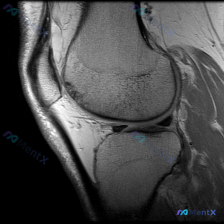

说软骨异常却没看到明显病灶?单张膝关节MRI读片的坑踩过吗

这是一张膝关节矢状位T1加权MRI图像,扫描范围覆盖髌股关节及部分胫股关节,图像对比度良好,可以清晰分辨解剖结构。

- 骨骼与对线:股骨远端、胫骨近端、髌骨骨皮质连续,没有明显骨折线;骨髓信号没有异常高低改变;髌股关节对合关系尚可,没有明显脱位半脱位。

- 关节软骨与半月板:股骨滑车、髌骨关节面软骨厚度正常,没有明显剥脱或缺损;本层面可见的半月板前角信号正常,没有达关节面的异常高信号,排除明显撕裂。

- 韧带与肌腱:髌韧带、股四头肌腱连续走行正常,没有增粗撕裂;可见的后交叉韧带形态信号正常,没有断裂征象。

- 关节囊与软组织:髌上囊、髌下脂肪垫周围没有异常积液信号;Hoffa脂肪垫信号均匀,没有炎性水肿;周围皮下肌肉都没有异常信号。

核心问题是:问题提示存在「软骨异常」,但我们在这张图里找不到明确的软骨病变证据。